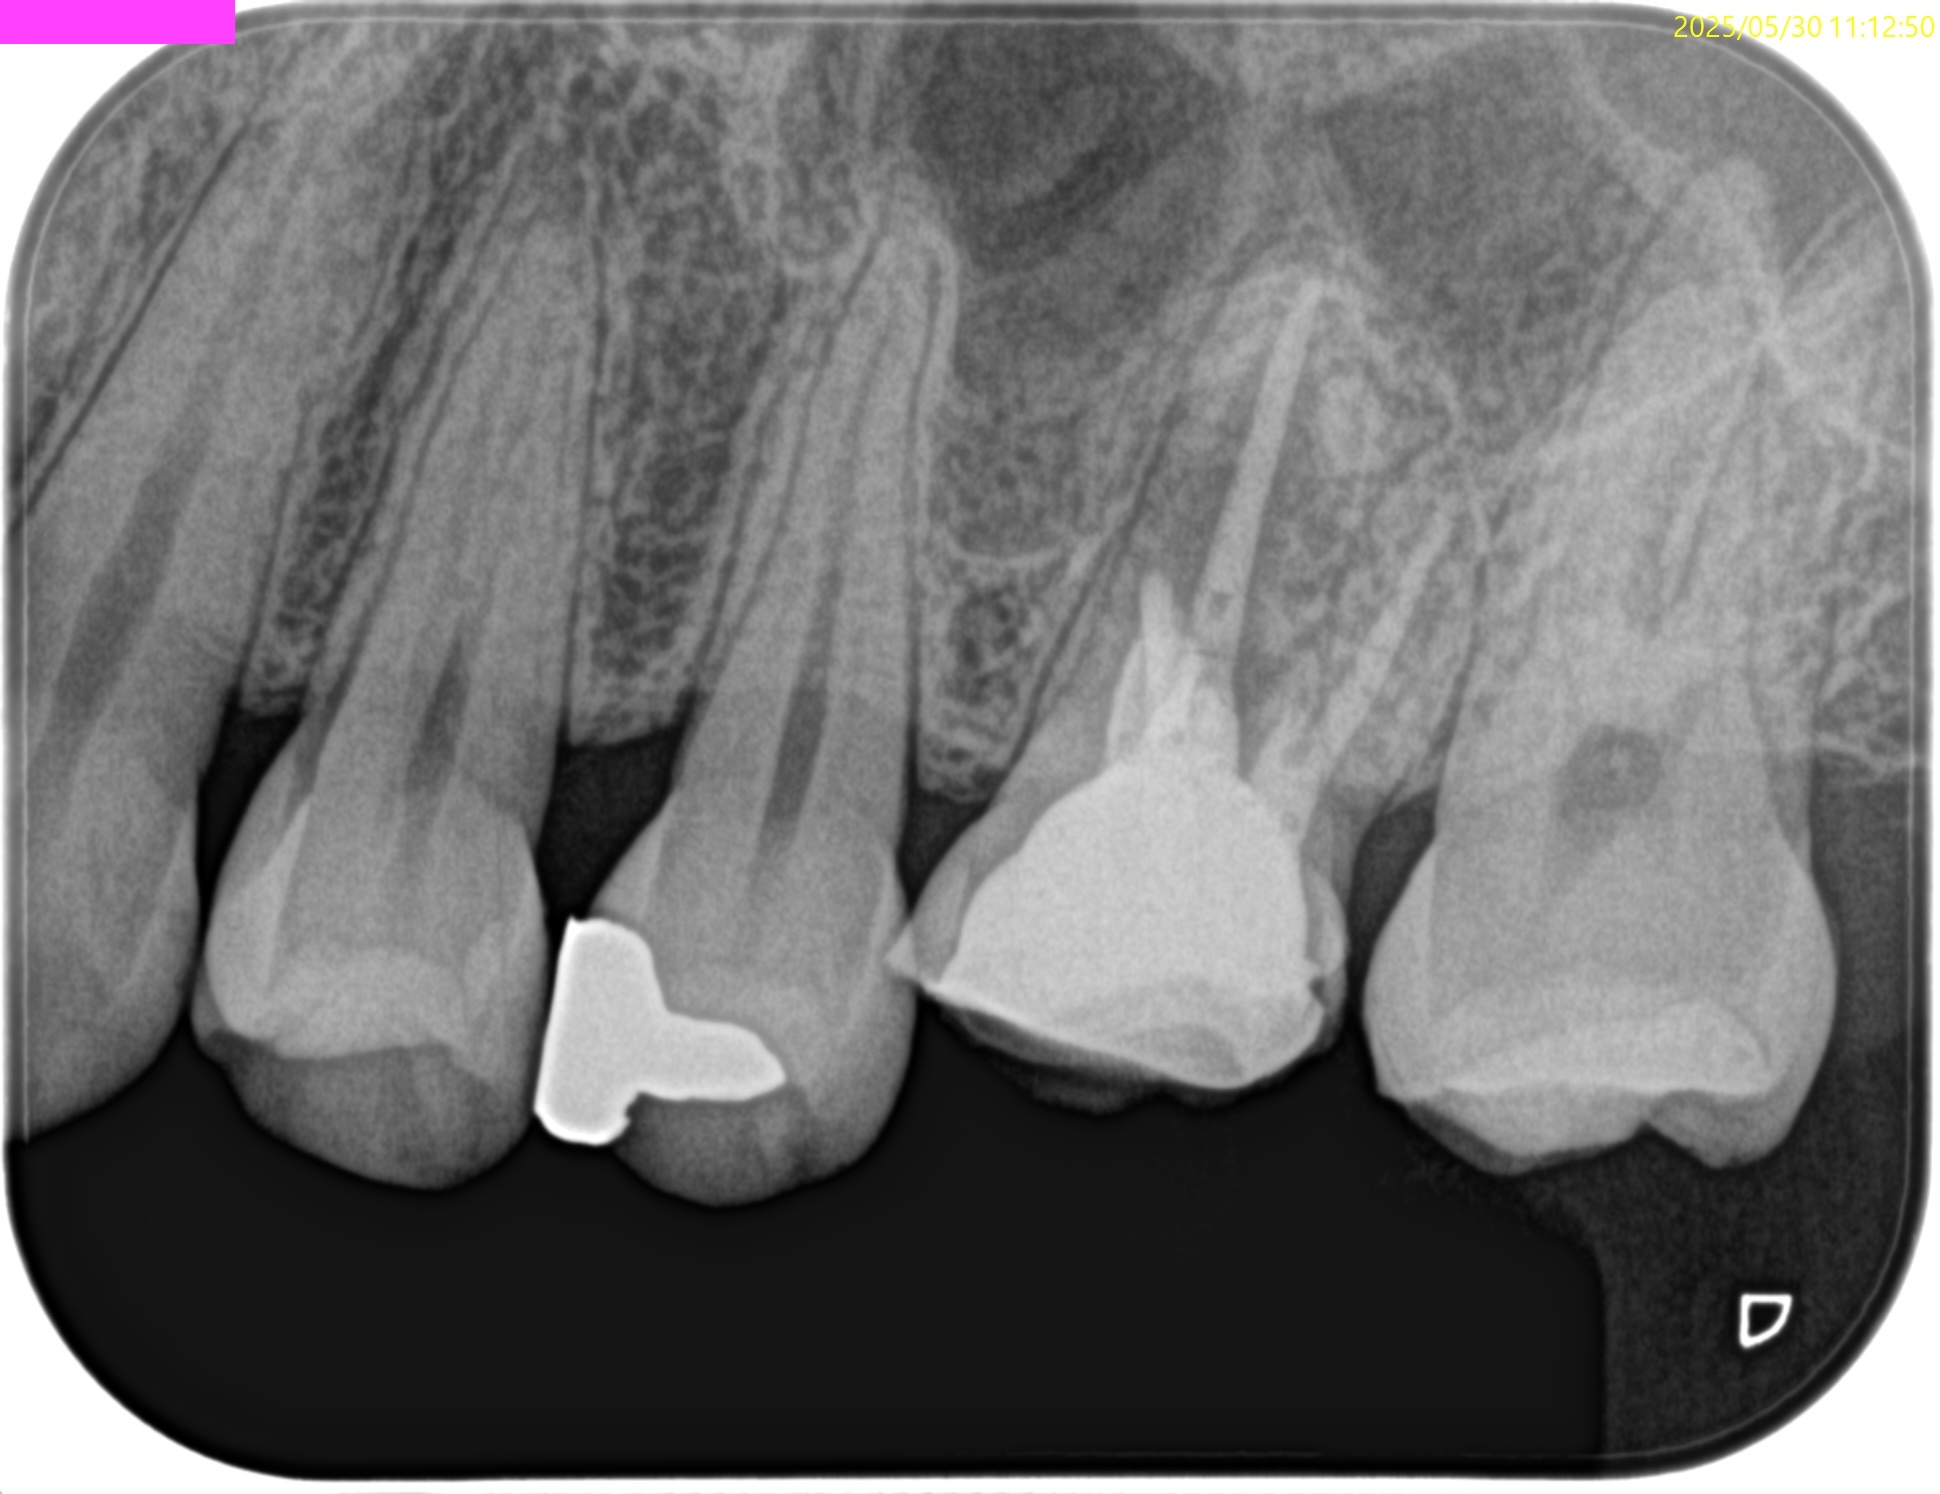

PA(2025.4.15)

MBの根管口の歯質が少ない。

垂直性歯根破折を惹起させるものだ。

#14 Core build up, Perforation Repair(2025.4.15)

MBは穿孔部ごとBC sealer, BC Puttyで充填した。

この後Apicoectomyになるから問題はない。

同日、MBのApicoectomyを行った。

MBのApexを見つけることなく、CEJから5.5mmの位置で頬舌的幅径5mmの長さで切断し、Apex周囲の骨を削除しApexを取り除いた。

術後にPA, CBCTを撮影した。

問題はないだろう。